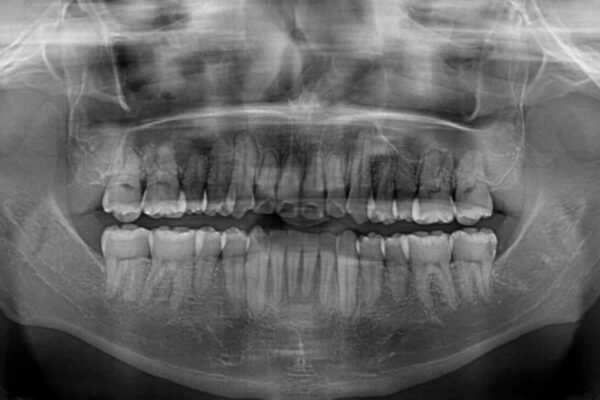

八重歯と前歯のクロスバイトを改善したいとのことで来院された患者様です。

デコボコの程度は強かったのですが、口元の突出感はなかったため、非抜歯矯正としました。

治療前

• 八重歯とクロスバイト 目立たないワイヤー装置で矯正治療 治療前画像